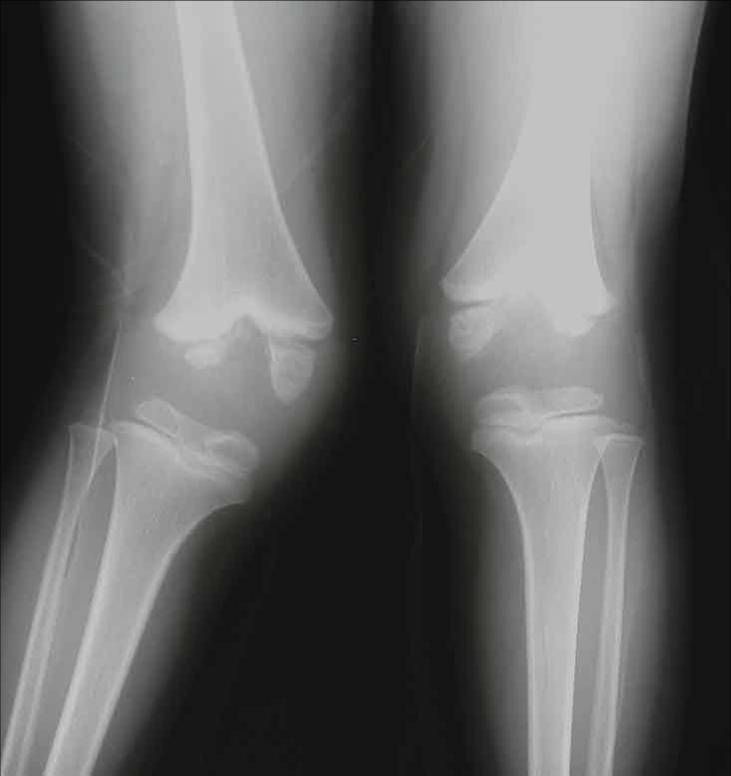

Unfortunately, there is no cure for hemophilic arthropathy, and there is no way to reverse the progression of the condition once it has begun. Surgical procedures such as joint replacements help with the symptoms of joint disease but will not return your joint to 100% normal functioning